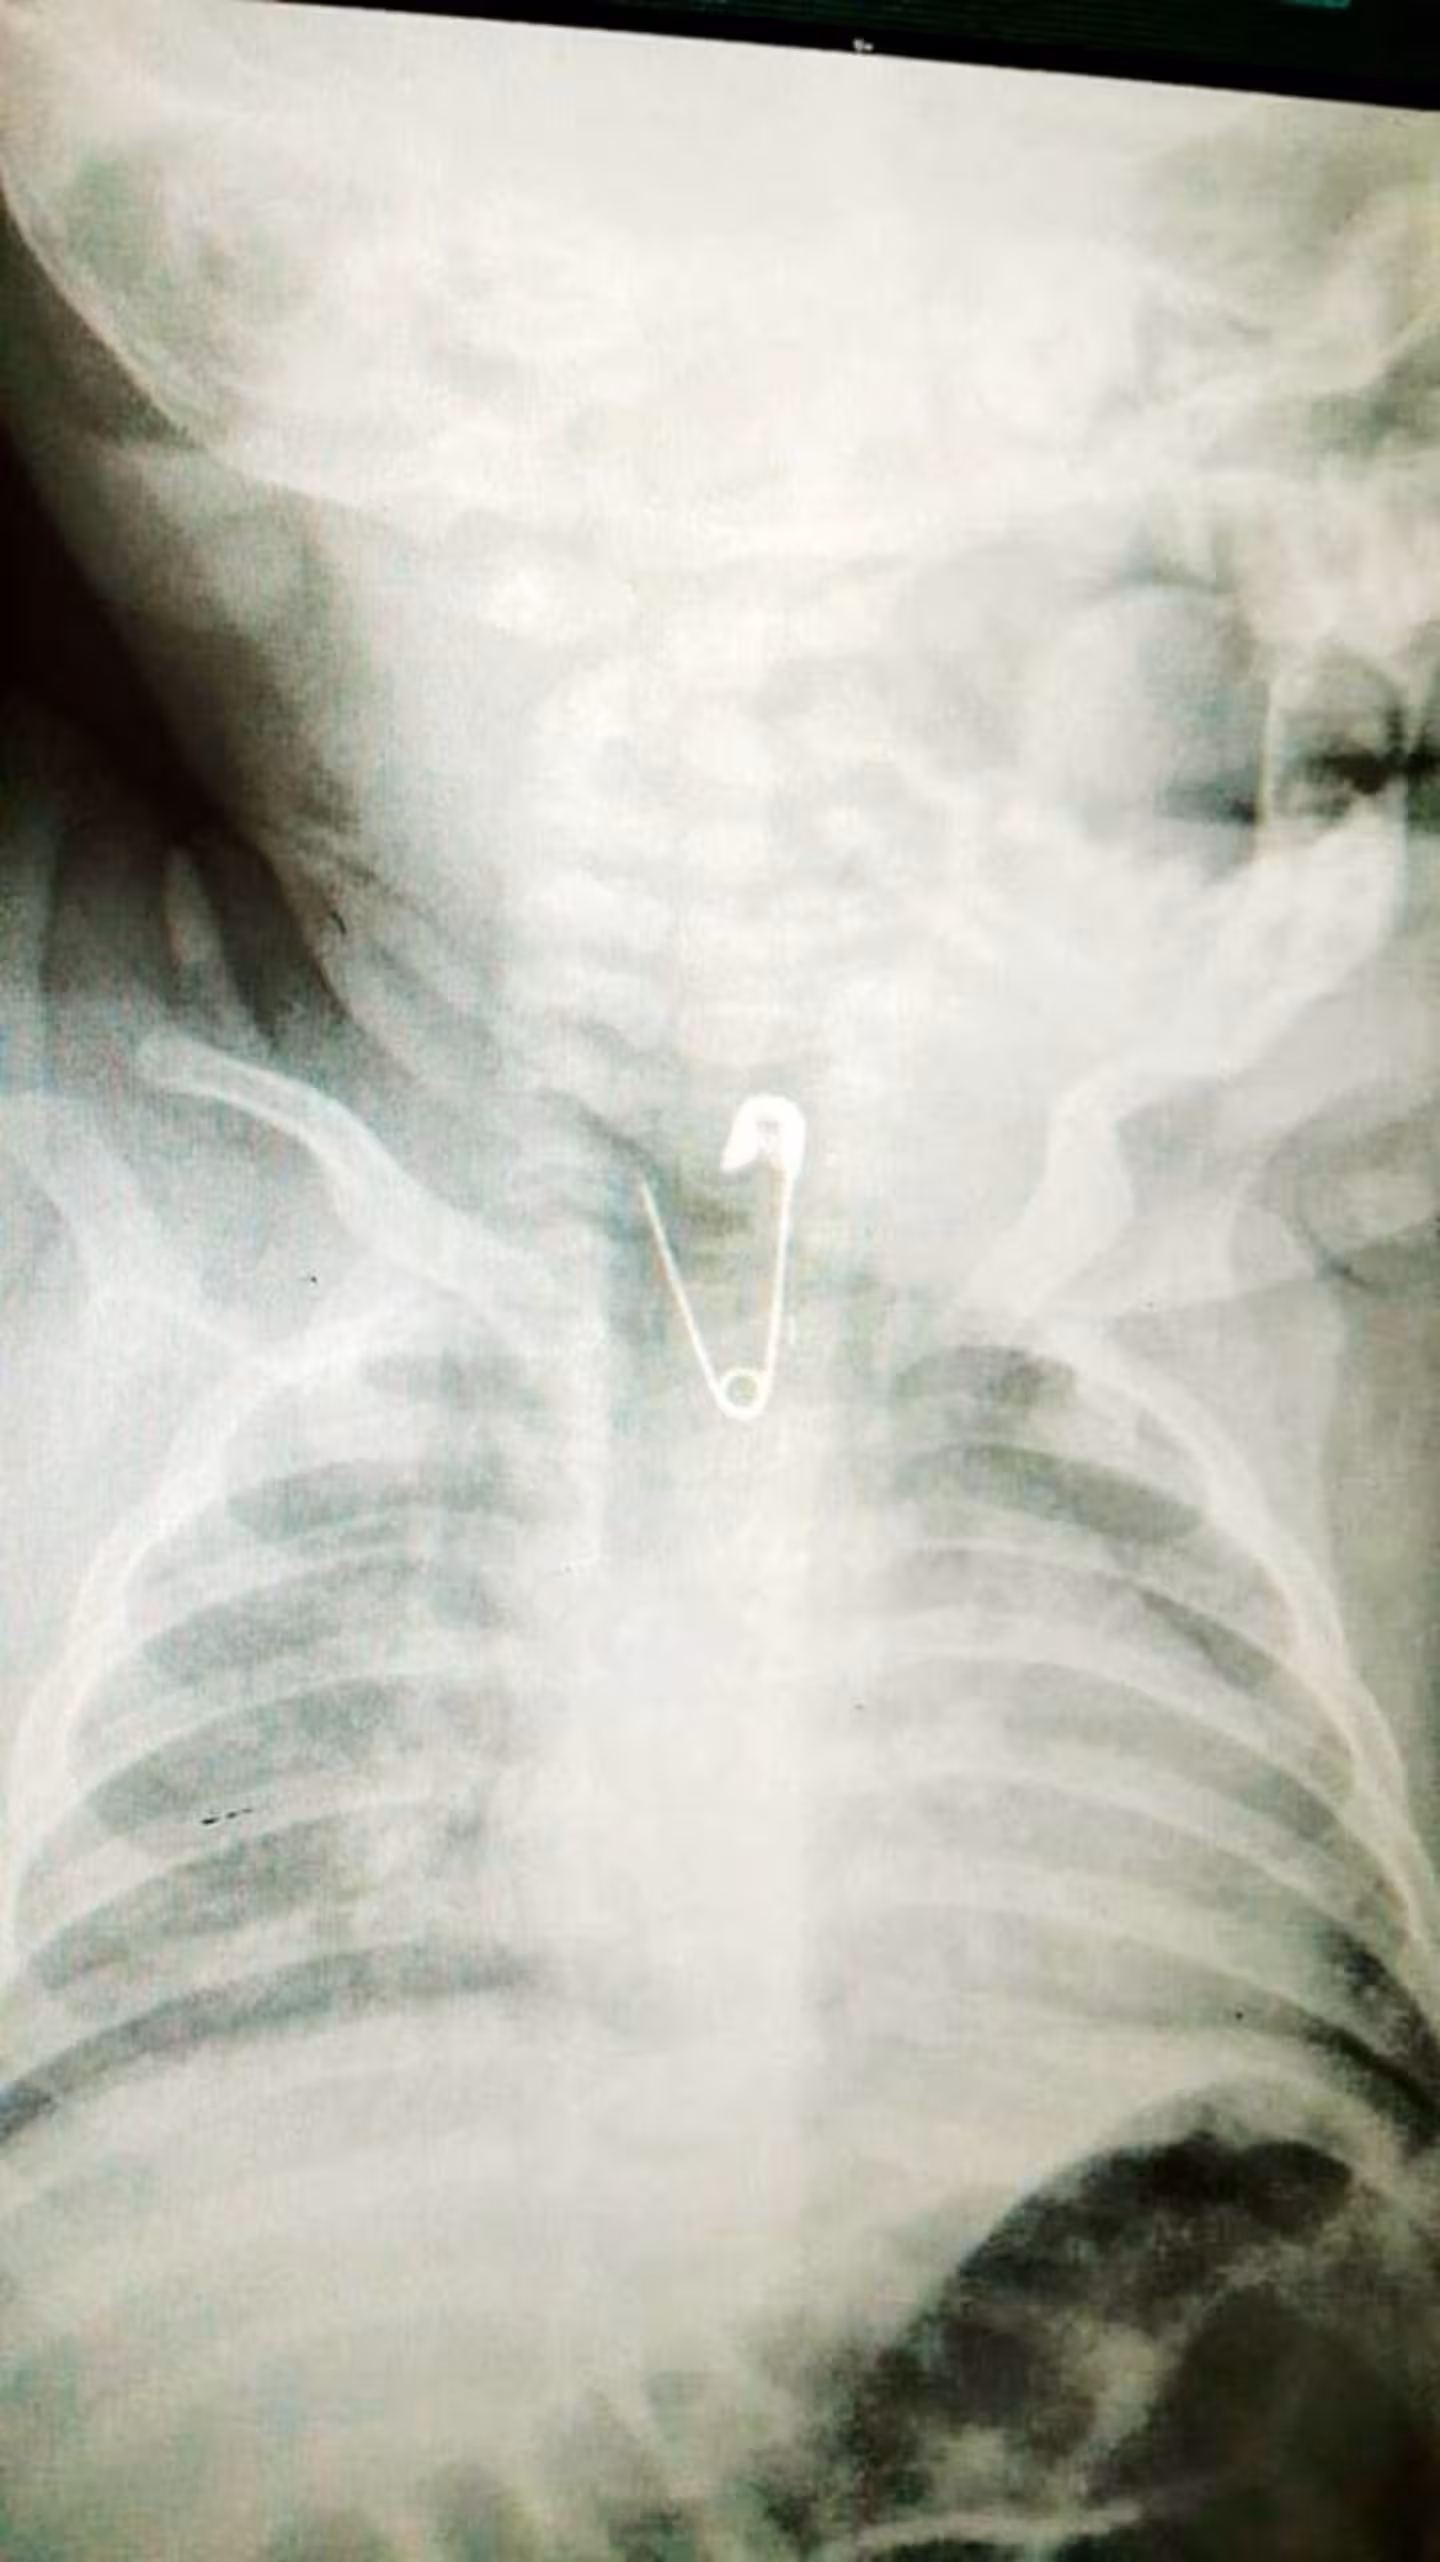

"Скажу чесно, коли через півгодини шпилька опинилася у нас в руках, а дівчинка, при цьому, була цілою і неушкодженою, ми були такі щасливі, що це навіть словами не передати”, — розповів лікар.